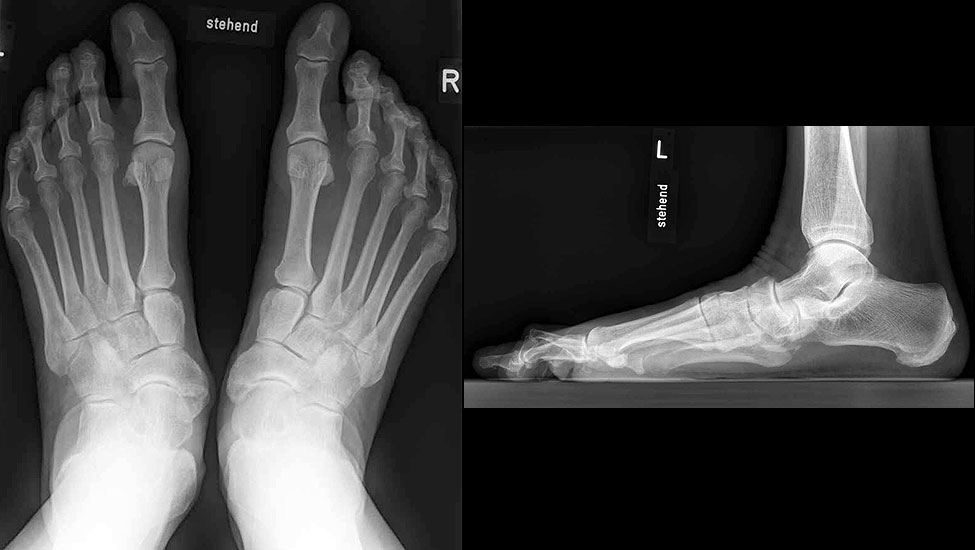

Konventionelles Röntgen

Stehende konventionelle Röntgenbilder eines Fußes mit Planovalgus Deformität Stadium II b dorsoplantar (dp) und seitlich. Auf der dp-Aufnahme zeigt sich die talo-calcaneare Divergenz, der gegenüber dem Kalkaneus nach anterior gleitende Talus und d

Stehende Aufnahmen des Fußes dorsoplantar (dp) und seitlich sowie des OSG anteroposterior (ap) sind die Grundlage der konventionellen Röntgendiagnostik (Abb. 5). Ergänzend werden gelegentlich die Rückfuβ-Alignement Aufnahme nach Saltzman 19 und Vergleichsaufnahmen der Gegenseite durchgeführt.

Der Talo-Metatarsale I Winkel bzw. die laterale talonaviculare Subluxation auf der stehenden dorsoplantaren Aufnahme des Fuβes dokumentieren das Ausmaβ des Vorfuβ abductus (Abb. 6 a,b). Ein dp Talo-Metatarsale I Winkel von > 10° (nach medial konvex) ist als pathologisch anzusehen. Mit der Bestimmung der talocalcanearen Divergenz (Abb. 6 c) erhält man ein Eindruck über das Ausmaβ des Rückfuβ valgus; eine leichte Divergenz bis ca. 12° gilt als physiologisch 20.

Auf der seitlichen, stehenden Aufnahme des Fußes wird ebenfalls der laterale Talo-Metatarsale I Winkel (Abb. 6 d) gemessen und so das kollabierte mediale Längsgewölbe dokumentiert. Auch hier gilt ein Talo-Metatarsale I Winkel von > 5° (nach plantar konvex) als pathologisch 21. Der Kollaps findet dabei meist im Talonaviculargelenk, seltener in der Naviculocuneiform-Gelenkreihe statt. Instabilität und Arthrose im 1. TMT sollten ausgeschlossen oder bei der Operationsplanung mit einbezogen werden. Weitere wichtige radiologische Messungen zur Beurteilung der Planovalgus-Statik und Progression der Deformität sind der laterale talo-calcaneare Winkel (Abb. 6 e) und der Abstand des Os cuneiforme-Unterrandes zum Untergrund (Abb. 6 f, Cuneiform height, 22. Eine anteriore Translation des Talus auf dem Kalkaneus findet man sowohl auf der ap, als auch auf der seitlichen Aufnahme des Fuβes mit Aufhebung der Cima-Linie.

Radiologisches Beispiel einer fixierten Planovalgus Deformität Stadium III, 51 jähriger Patient. Stehendes präoperatives Röntgenbild und 1 Jahr postoperatives Röntgenbild des Fußes seitlich. Die Korrektur der Deformität umfaßte eine leicht korrigierende U

Abbildung 12